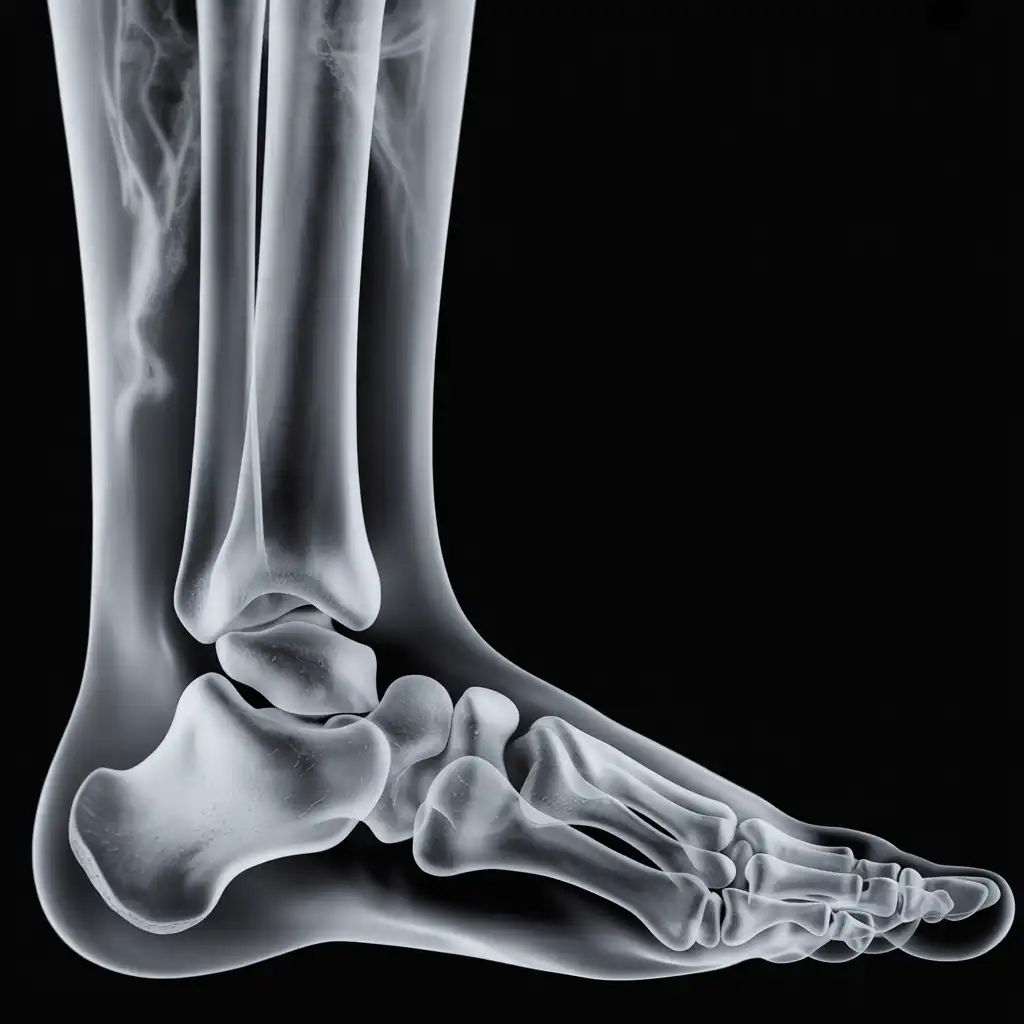

Da anni offriamo un servizio di radiografie a domicilio pensato per garantire ai nostri pazienti la stessa qualità diagnostica degli esami eseguiti in ospedale, ma con la comodità e la sicurezza della propria casa.

Abbiamo effettuato migliaia di esami direttamente presso abitazioni, residenze e strutture assistenziali, utilizzando apparecchiature digitali portatili certificate e procedure rapide e sicure.